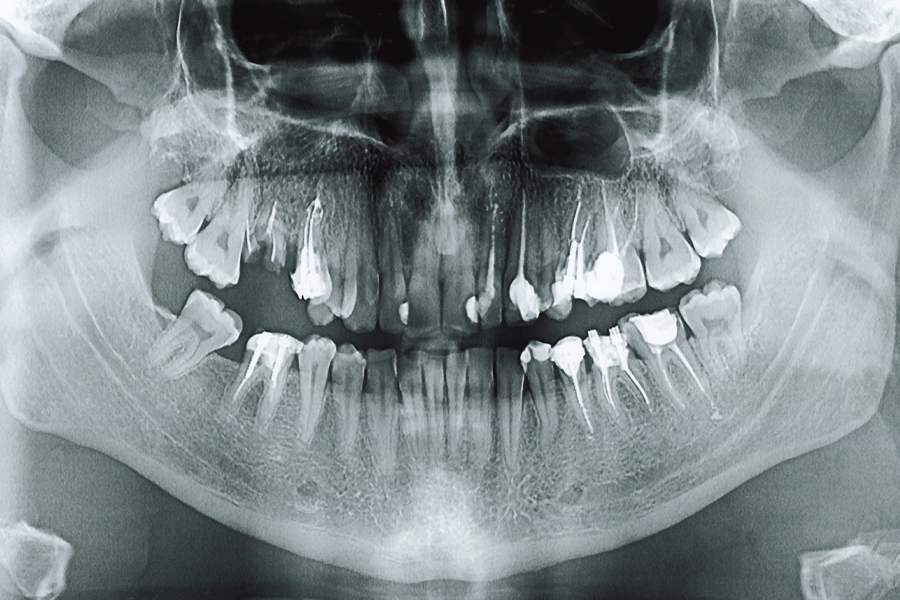

検査

口の中を直接拝見したり、レントゲンや歯周ポケット検査等で現状の把握をさせてください。